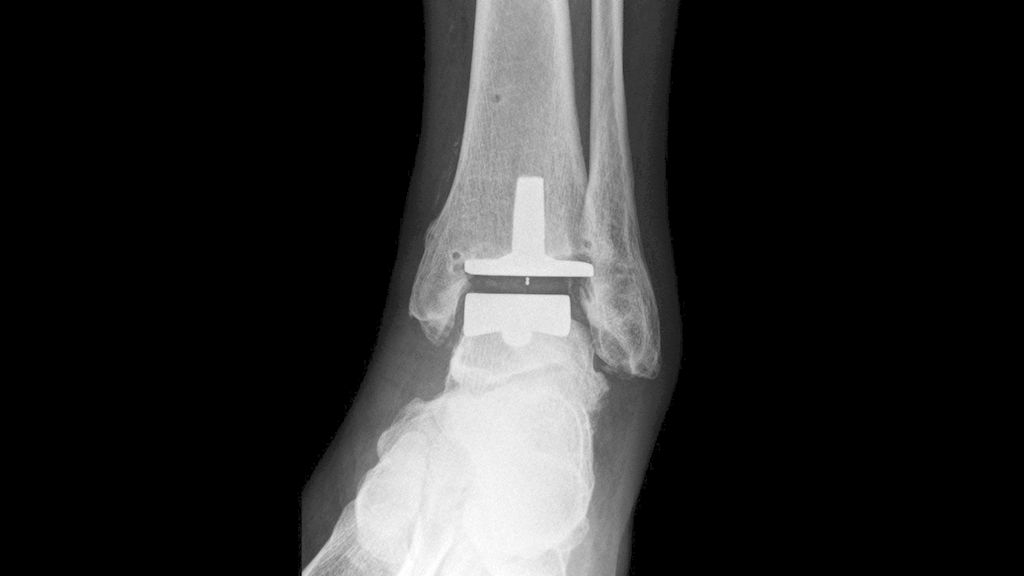

Von unserer Arbeitsgruppe wurden in den Jahren 2009–2019 92 Triple-A-Sprunggelenksprothesen implantiert. Die Triple-A-Prothese ist eine zementfreie 3-Komponenten-Prothese mit einer sphärischen Resektion des Talus, einer Stem-fixierten Tibia und einem zentral geführten mobilen Polyethylen-Inlay (Abb. 3).